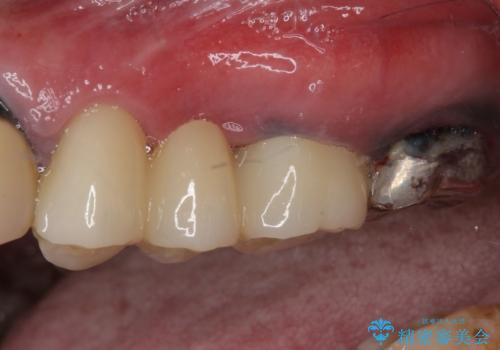

銀歯の適合が悪く、土台の歯に虫歯多く残っていたので、虫歯除去とファイバーコアによる土台植立を行い、フルジルコニア製ブリッジを装着することとしました。

ずっと気になっていた手前の銀歯が自然な歯の色となり、笑うときのヒトの目線が気にならなくなりました。

他にも気になる銀歯があるので、治療を検討していきたいとのことでした。